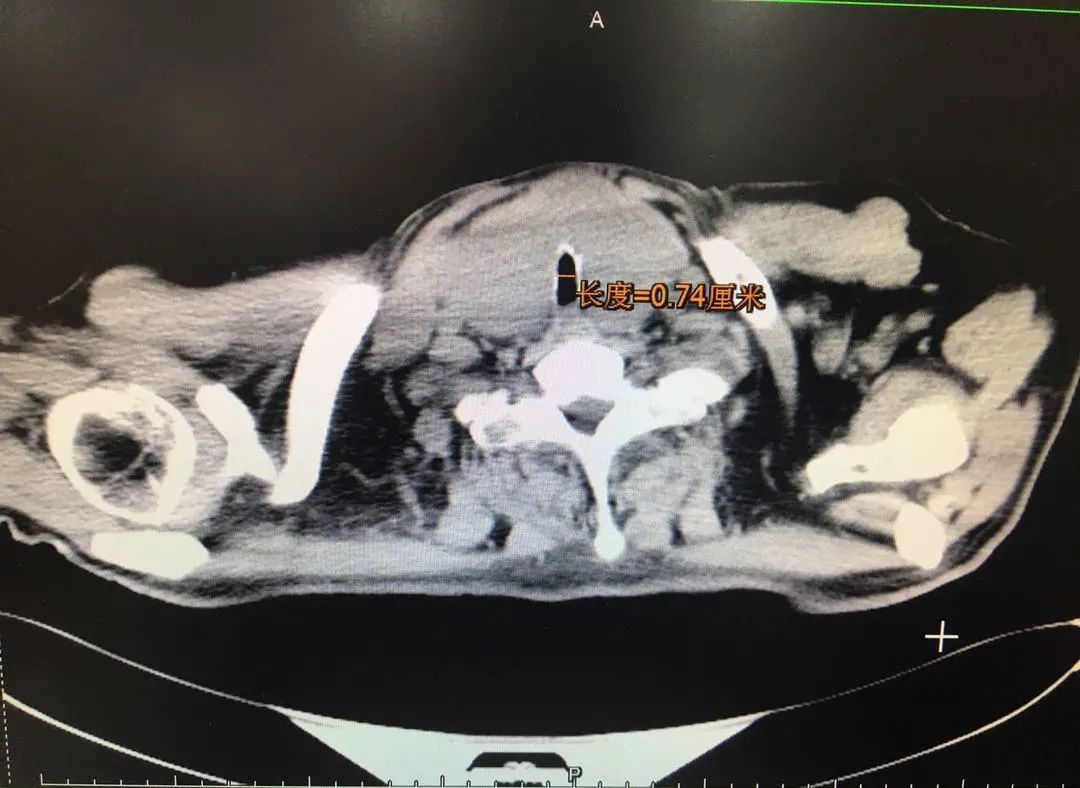

原来,他去年做过一次声门型喉癌手术,右侧声带已切,整个喉咙的生理结构已经严重变形,而且术后气管切开,气道内外形成很多疤痕,从CT上看气管狭窄处只有几毫米,别说开刀,就连平时生活都很容易窒息。

对麻醉科来说,气管狭窄的困难插管压力巨大。张富军主任仔细观察着喉镜检查视频,喉镜下看已经不是顺畅的气管通道,而是层层叠叠互相交错的粘膜,再看下去发现原来并不是CT显示的那么狭窄,还是有7毫米的空间哒!综合CT和喉镜检查结果后他果断拍板,可以插管!为了确保安全,还特地从厂方调拨来6毫米的神经检测气管导管。